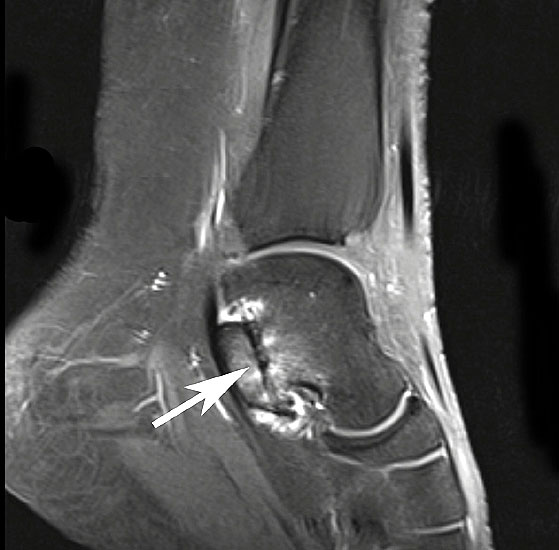

MRT mit KM bei Split der Peronaeus brevis Sehne in Höhe der Fibulaspitze

Abbildung 13

Klassischerweise beginnt eine Peronealsehnenruptur mit einem Distorsionstrauma. Bei dieser Verletzung kommt es zunächst zu einer Längsruptur (Peroneus-Split) der Peronaeus brevis Sehne in Höhe der Fibulaspitze. Bestehen nun Risikofaktoren wie eine persistierende Instabilität des Sprunggelenks oder ein bis zu diesem Zeitpunkt asymptomatischer Rückfußvarus, kommt bei jeder weiteren Distorsion zu einer Zunahme des Sehnenschadens bis hin zur vollständigen Kontinuitätsunterbrechung 38. Für das Peronaeus Split Syndrom gibt es kein klassisches Leitsymptom. Wichtig ist bei anhaltenden Beschwerden nach einem Distorsionstrauma an diese Differentialdiagnose zu denken und ein MRT mit Kontrastmittel zu veranlassen 39.